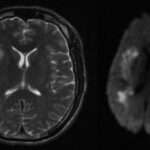

El sulfato de magnesio es un medicamento que se ha utilizado comúnmente en el manejo del trabajo de parto prematuro como un agente tocolítico, aunque ya no se recomienda como primera línea de tratamiento. Sin embargo, se ha observado que este fármaco puede ofrecer beneficios adicionales, especialmente en la protección contra la parálisis cerebral en recién nacidos que han sido gestados entre las 24 y 32 semanas de gestación, cuando se administra en el momento del parto.